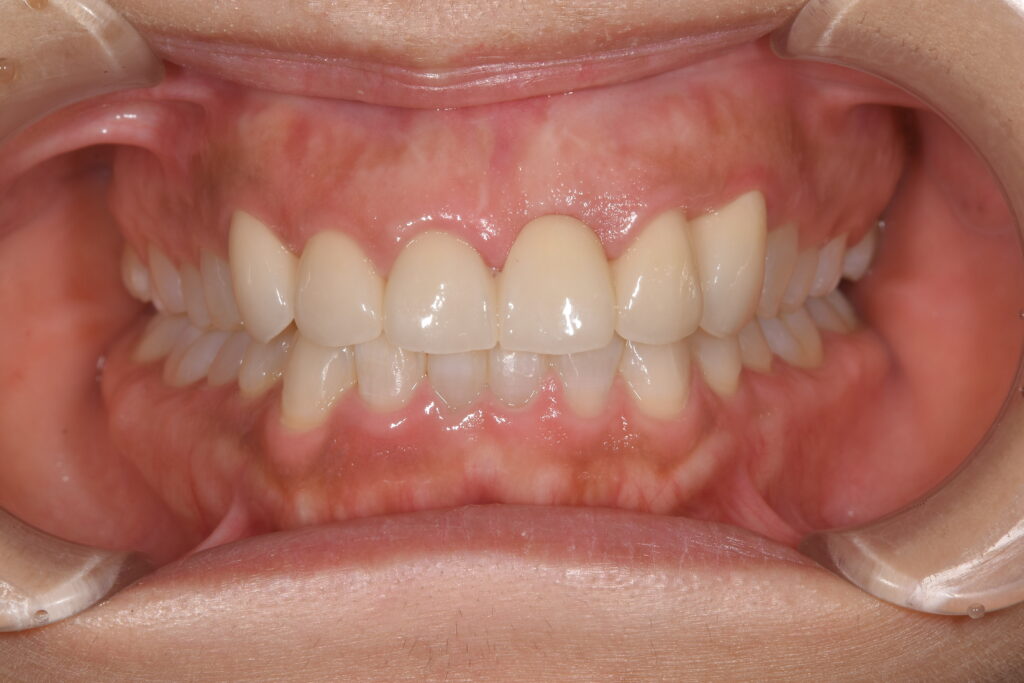

【治療終了時】

④矯正終了後、上顎前歯は歯茎を整える手術施行。仮歯調整。

⑤上顎左3番目から右側3番目の歯(計6本)をセラミック(ジルコニア)を装着。

また、治療内容④で記載した、歯茎を整える手術。これは初診時と治療終了後の上顎の歯茎のラインを注視して下さい。差は歴然ではないでしょうか。今回の患者様は、笑った際に歯茎が少し見える方でした。ですので、歯茎の見え方にも細心の注意を行い、このような処置を行った次第です。